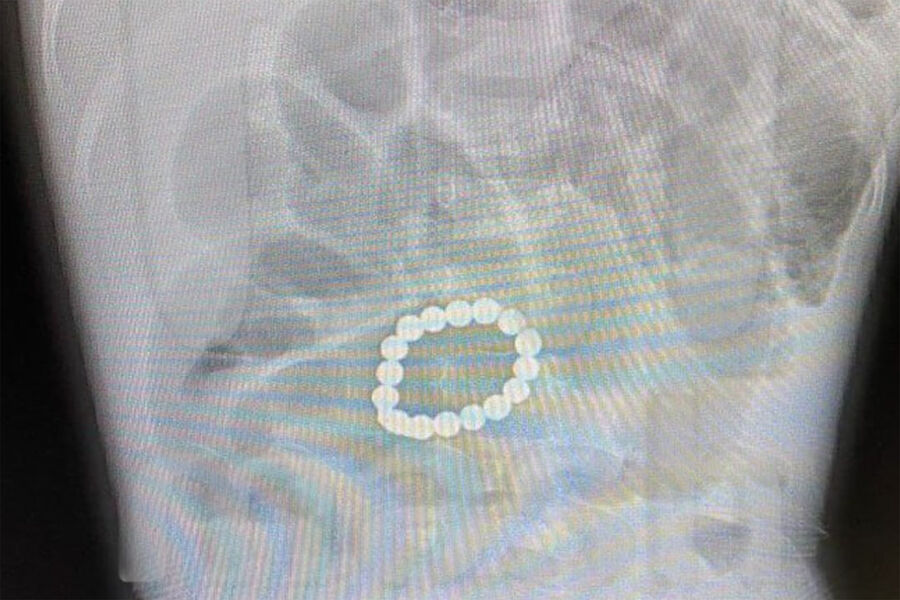

Хирурги Подмосковья спасли ребенка, который проглотил 15 магнитов

В Подмосковье врачи извлекли из кишечника ребенка 15 магнитов

В учреждении специалисты назначили УЗИ и выяснили, что в желудке находятся 15 небольших магнитов. Из-за инородных тел желудок пациента практически не работал.